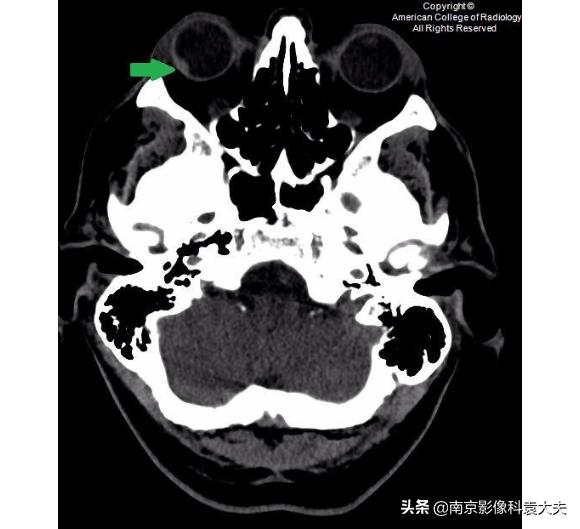

上图 在晶状体水平轴位非对比CT图像显示右眼前房(圆环)前后径减小,临床上可在角膜裂伤的情况下看到。

上图 眼球轴位非对比CT图像显示右侧眼睑外侧或巩膜表面可见点状异物(黄圈),发现巩膜上异物,我们应提高对角膜裂伤或其他眼球损伤的怀疑程度。

非对比增强CT(平扫)更低一层面显示沿右眼球外侧壁的高密度的眼内出血(箭头)。眼内出血可能是眼外伤的一